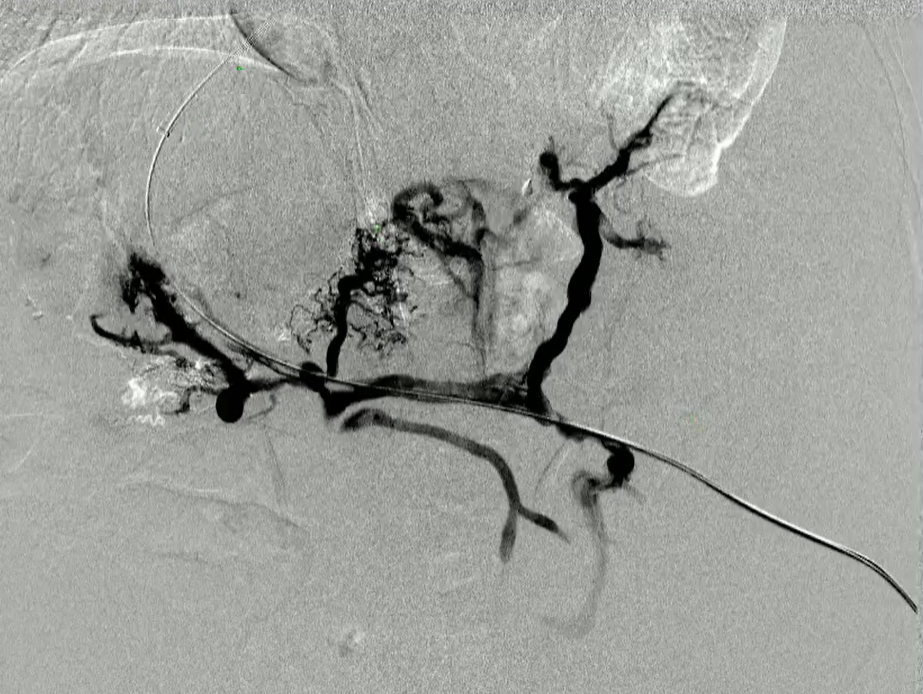

该程序包含以下步骤: 经脾脏入路:在超声引导下,刺穿脾静脉内的一个实质内分支。 在通过脾静脉造影确认了静脉通路后,导管和导丝被推进,以穿过脾静脉并抵达血栓化的门静脉。在门静脉/右门静脉分支处放置圈套器,为TIPS穿刺精准定位。TIPS穿刺圈套器,并穿过圈套器完成TIPS

步骤: 鉴于慢性血栓形成的复杂性: 一种经脾脏途径的门静脉再通术(PVR)。 随后是经颈静脉肝内门体分流术 。

结果:术后影像学检查显示门静脉和脾静脉的血流情况有所改善,且残留血栓极少。

通过经颈静脉肝内门体分流术(TIPS)治疗慢性门静脉血栓时所涉及的技术复杂性和决策难题,尤其是在标准方法因血栓程度过重而无法实施的情况下更是如此。 采用脾经脏穿刺术治疗门静脉高压症的方法证明能够有效克服这些难题,从而成功实施了经颈静脉肝内门体分流术(TIPS)。 PVR-TIPS 作为一线治疗方案:PVR-TIPS 为慢性门静脉血栓的治疗提供了一种技术上可行的解决方案,克服了标准 TIPS 安装所面临的难题。 持久效果:该干预措施不仅恢复了门静脉的血流,而且在后续随访中还显示出持续的通畅性以及血栓的完全消散。